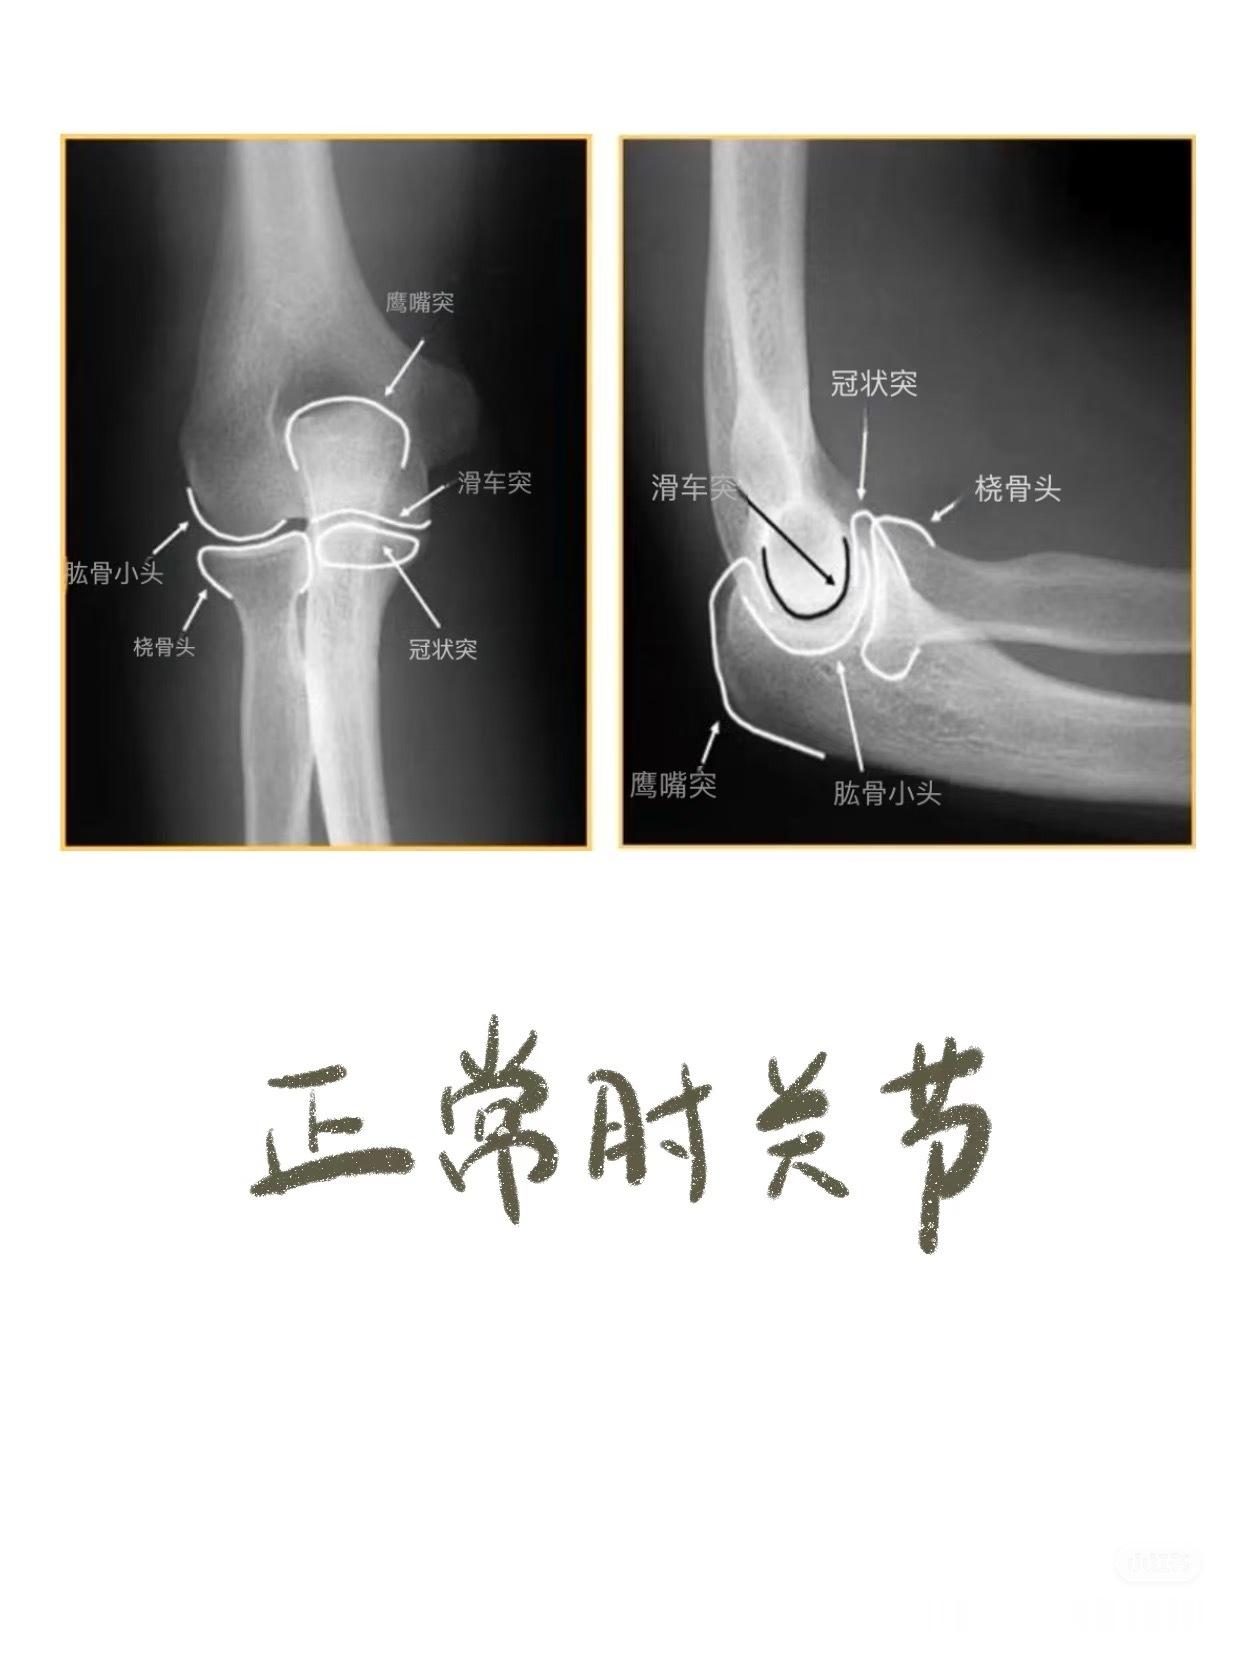

之前讲到影像学片子,膝盖和腰椎比较多,今天说些比较小众的——锁骨骨折,肘关节脱位,手部损伤等等👇🏻👇🏻【锁骨骨折的典型症状】01.疼痛与压痛——骨折部位出现持续性或阵发性剧烈疼痛。02.肿胀与皮下瘀斑——骨折后局部软组织损伤和出血,导致肿胀迅速出现,可能伴随皮下瘀血或青紫。03.畸形与异常活动——锁骨缩短、成角或旋转畸形,如骨折端上翘、隆起或凹陷。04. 活动受限——上肢抬举、伸展等功能受限,肩关节活动时疼痛加剧,甚至完全无法活动。05. 骨擦音/骨擦感——骨折断端摩擦时可触及异常活动或听到骨擦音,是骨折的典型体征。【肘关节脱位】01. 关节畸形——后脱位(最常见):尺骨鹰嘴向后突出,肘前窝饱满,前臂外观缩短,呈“靴状畸形”。——侧方脱位:肘关节向内或向外偏斜,形成肘内/外翻畸形。02. 肘后三角关系破坏 ——正常肘关节屈曲时,肱骨内/外上髁与尺骨鹰嘴构成等腰三角形;伸直时三点成一直线。——脱位后此关系完全失常。03. 弹性固定 ——关节被周围紧张韧带“锁扣”于半屈位,被动活动时有弹簧样阻力感。04. 骨性标志异常 ——后脱位时可触及肘后空虚感,尺骨鹰嘴异常隆起;——前脱位可触及肱骨远端。【手部骨折】拳击手骨折——握拳撞击——通常发生在第五掌骨(cr.骨科小龙笔记)大家如果还有关于骨折或者其他身体损伤的问题,都可以下方留言讨论